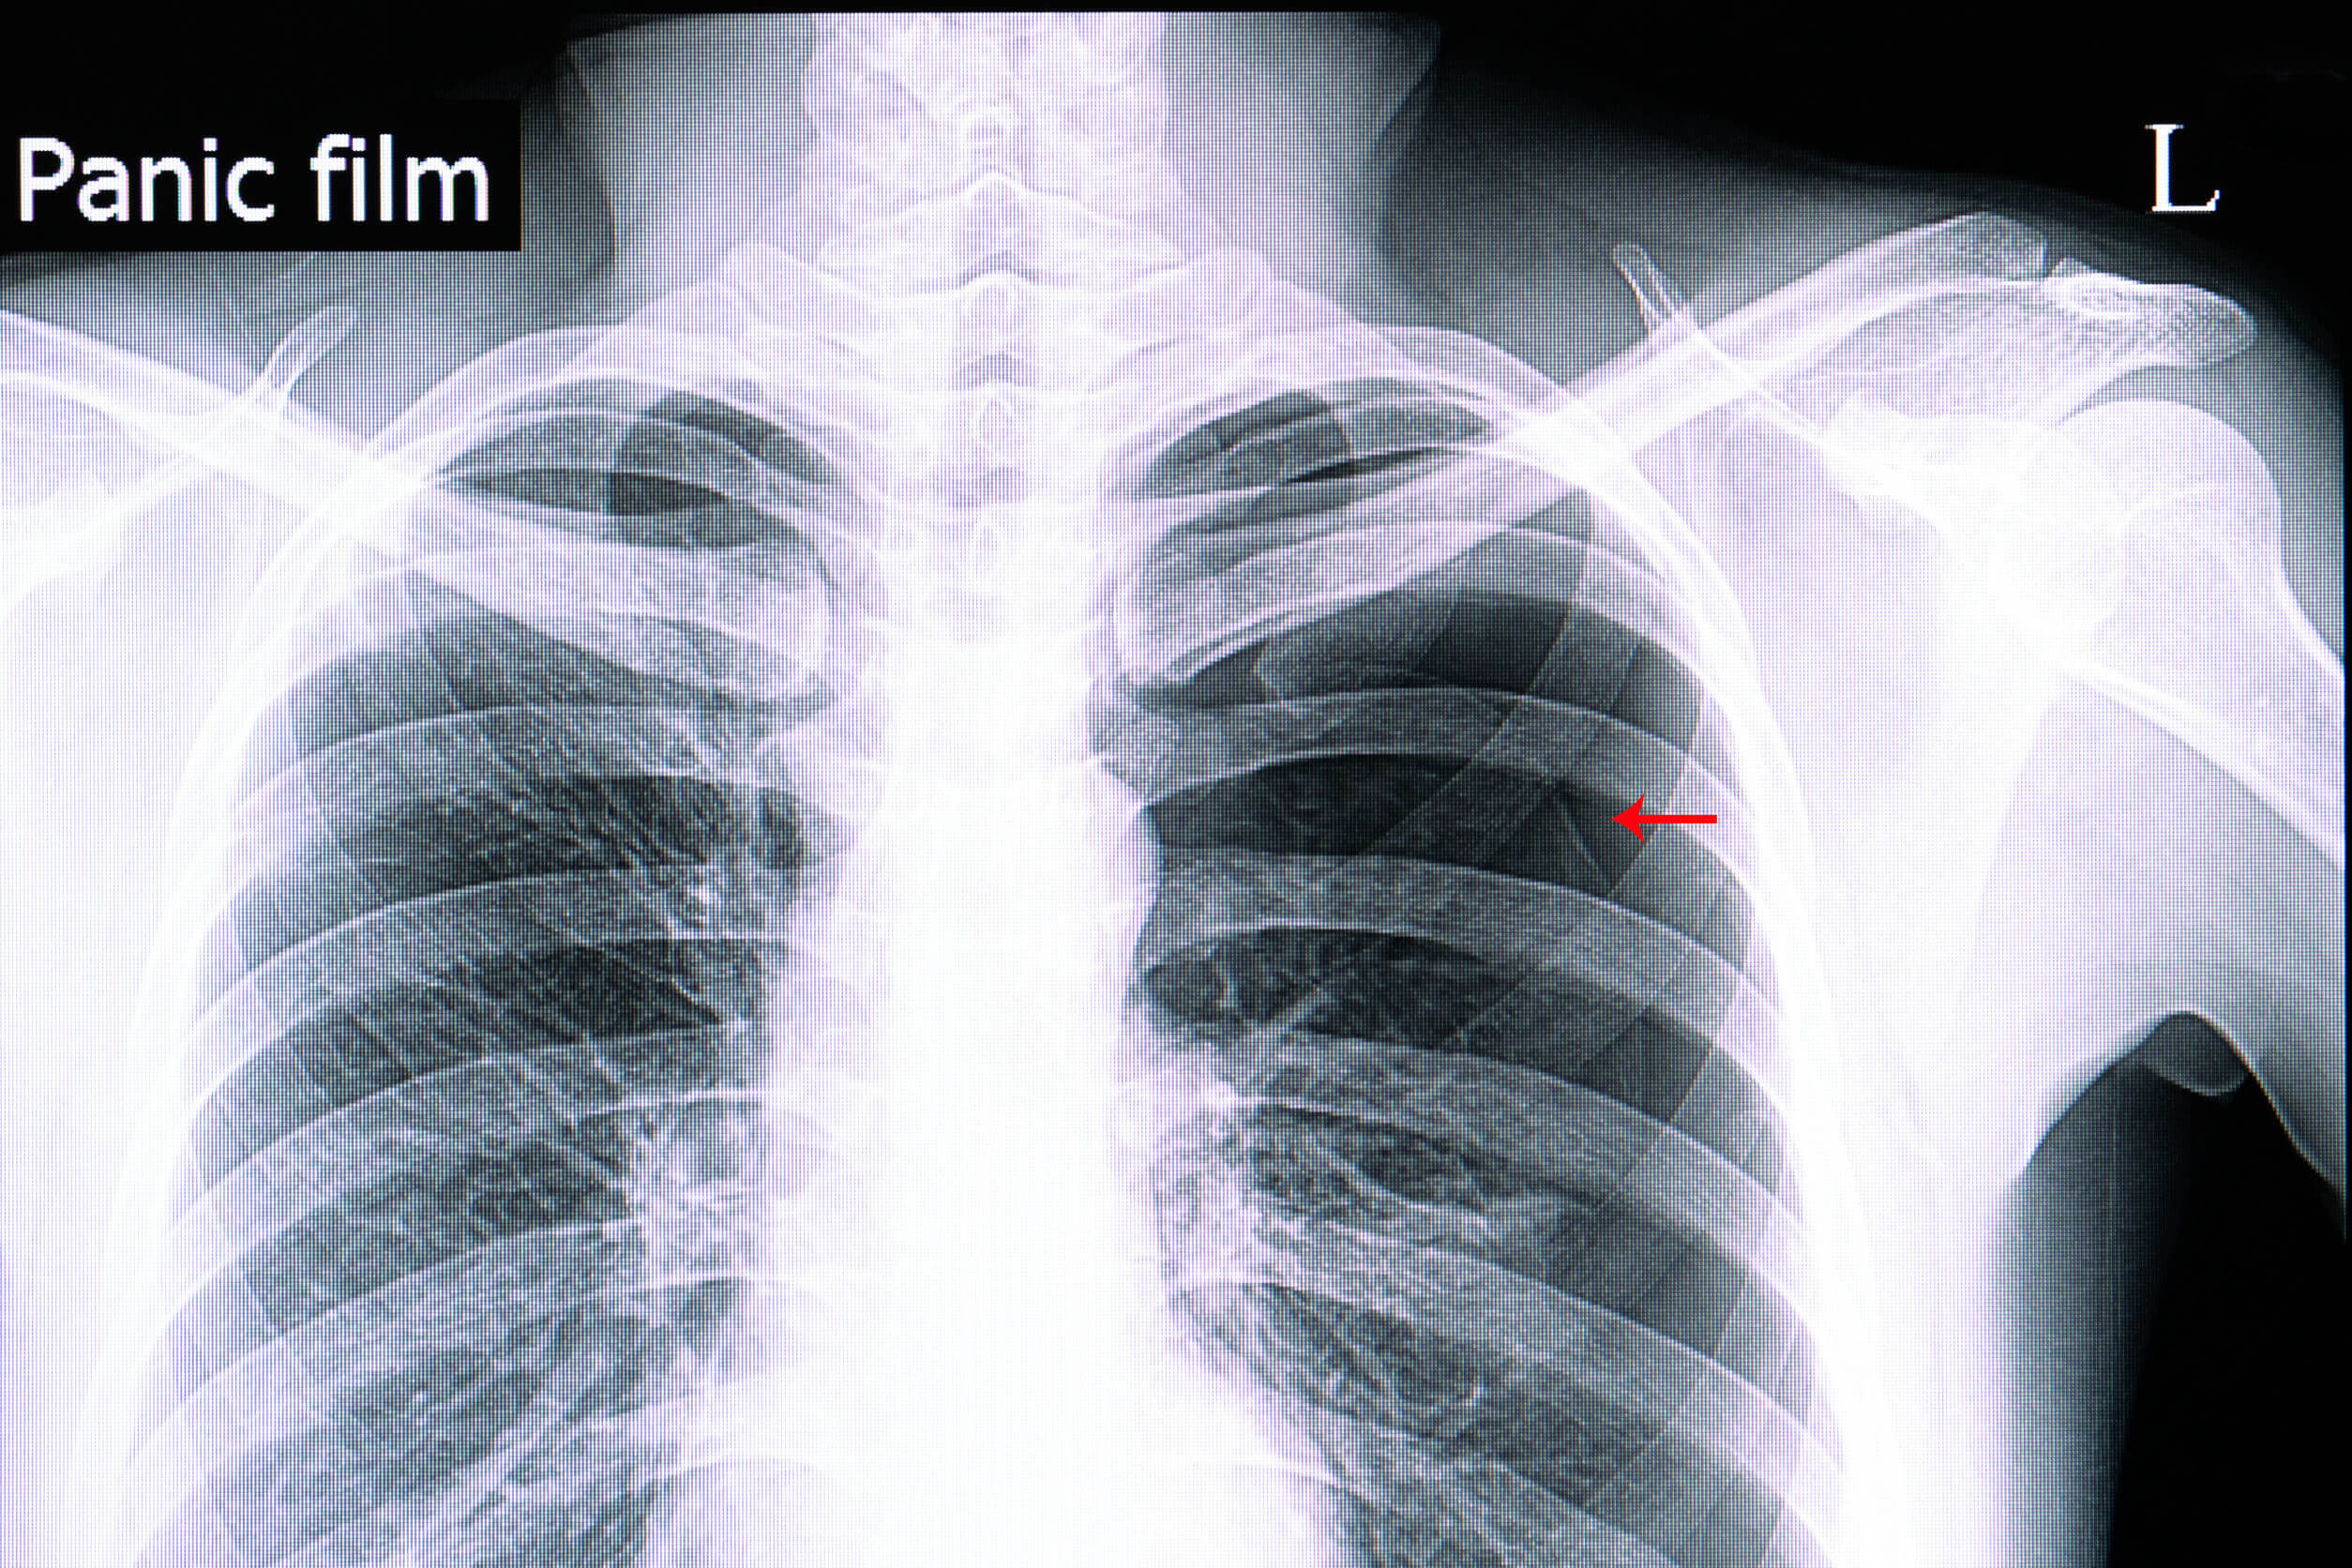

Diagnóstico del neumotórax

En la gran mayoría de los casos, el diagnóstico es clínico. Se puede recurrir a algunos estudios complementarios solo en aquellos casos en los que no esté comprometida la vida del paciente de forma inmediata.

De estos, la radiografía simple de tórax es la más indicada. El colapso tanto del pulmón como de sus estructuras vasculares suele ser muy evidente, a pesar de que en ciertos pacientes pudiese pasar desapercibido. En este último caso, el uso de una tomografía computarizada puede ser beneficioso.